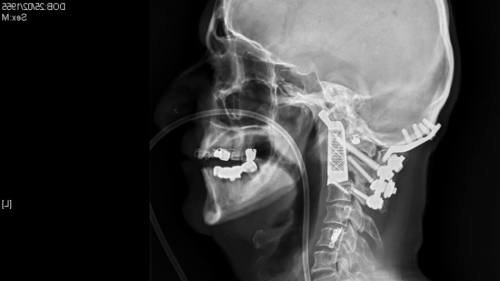

中新网2月26日电 据外媒报道,人体器官移植频传福音,3D打印再写医疗新里程。澳大利亚医生为一名患了癌症的男子进行一项全球第一例手术,替他移除被癌细胞严重破坏的椎骨,再为他植入一条用3D打印技术打印出来旳椎骨。该病人现时康复的进展良好,重获新生。

据报道,病人约塞夫斯基患了脊索瘤,是一种十分罕见的癌症。癌细胞攻击他的脊椎和头骨,并在他的颈项上方位置生长,令他饮食和说话都有困难。医学界估计,每100万人当中,只有一人患上这种病。

去年12月,神经科医生莫布斯为他进行长达15小时的手术,移除本来的椎骨,植入3D打印的脊骨。

莫布斯称,“如果不动手术,又不进行其他针对肿瘤的治疗话,这名病人的情况会转坏,甚至会有死亡的危险。”他说,再拖下去,约塞夫斯基的手脚也会无法活动,甚至会逐渐丧失呼吸的能力。

莫布斯形容手术过程极之复杂和艰辛。手术开始之前,他也无法确定约塞夫斯基是否能保住生命。手术最终取得成功,令他和病人的家人都松一口气。

如今已经两个多月过去了,约塞夫斯基的恢复情况相当不错,他的脖子已经能够活动,不过现在吃东西和说话还有问题,估计还要几个月才能痊愈。

不过,其亲人们认为约塞夫斯基的身体在手术后每天都在进步,其说话能力也在逐渐恢复。